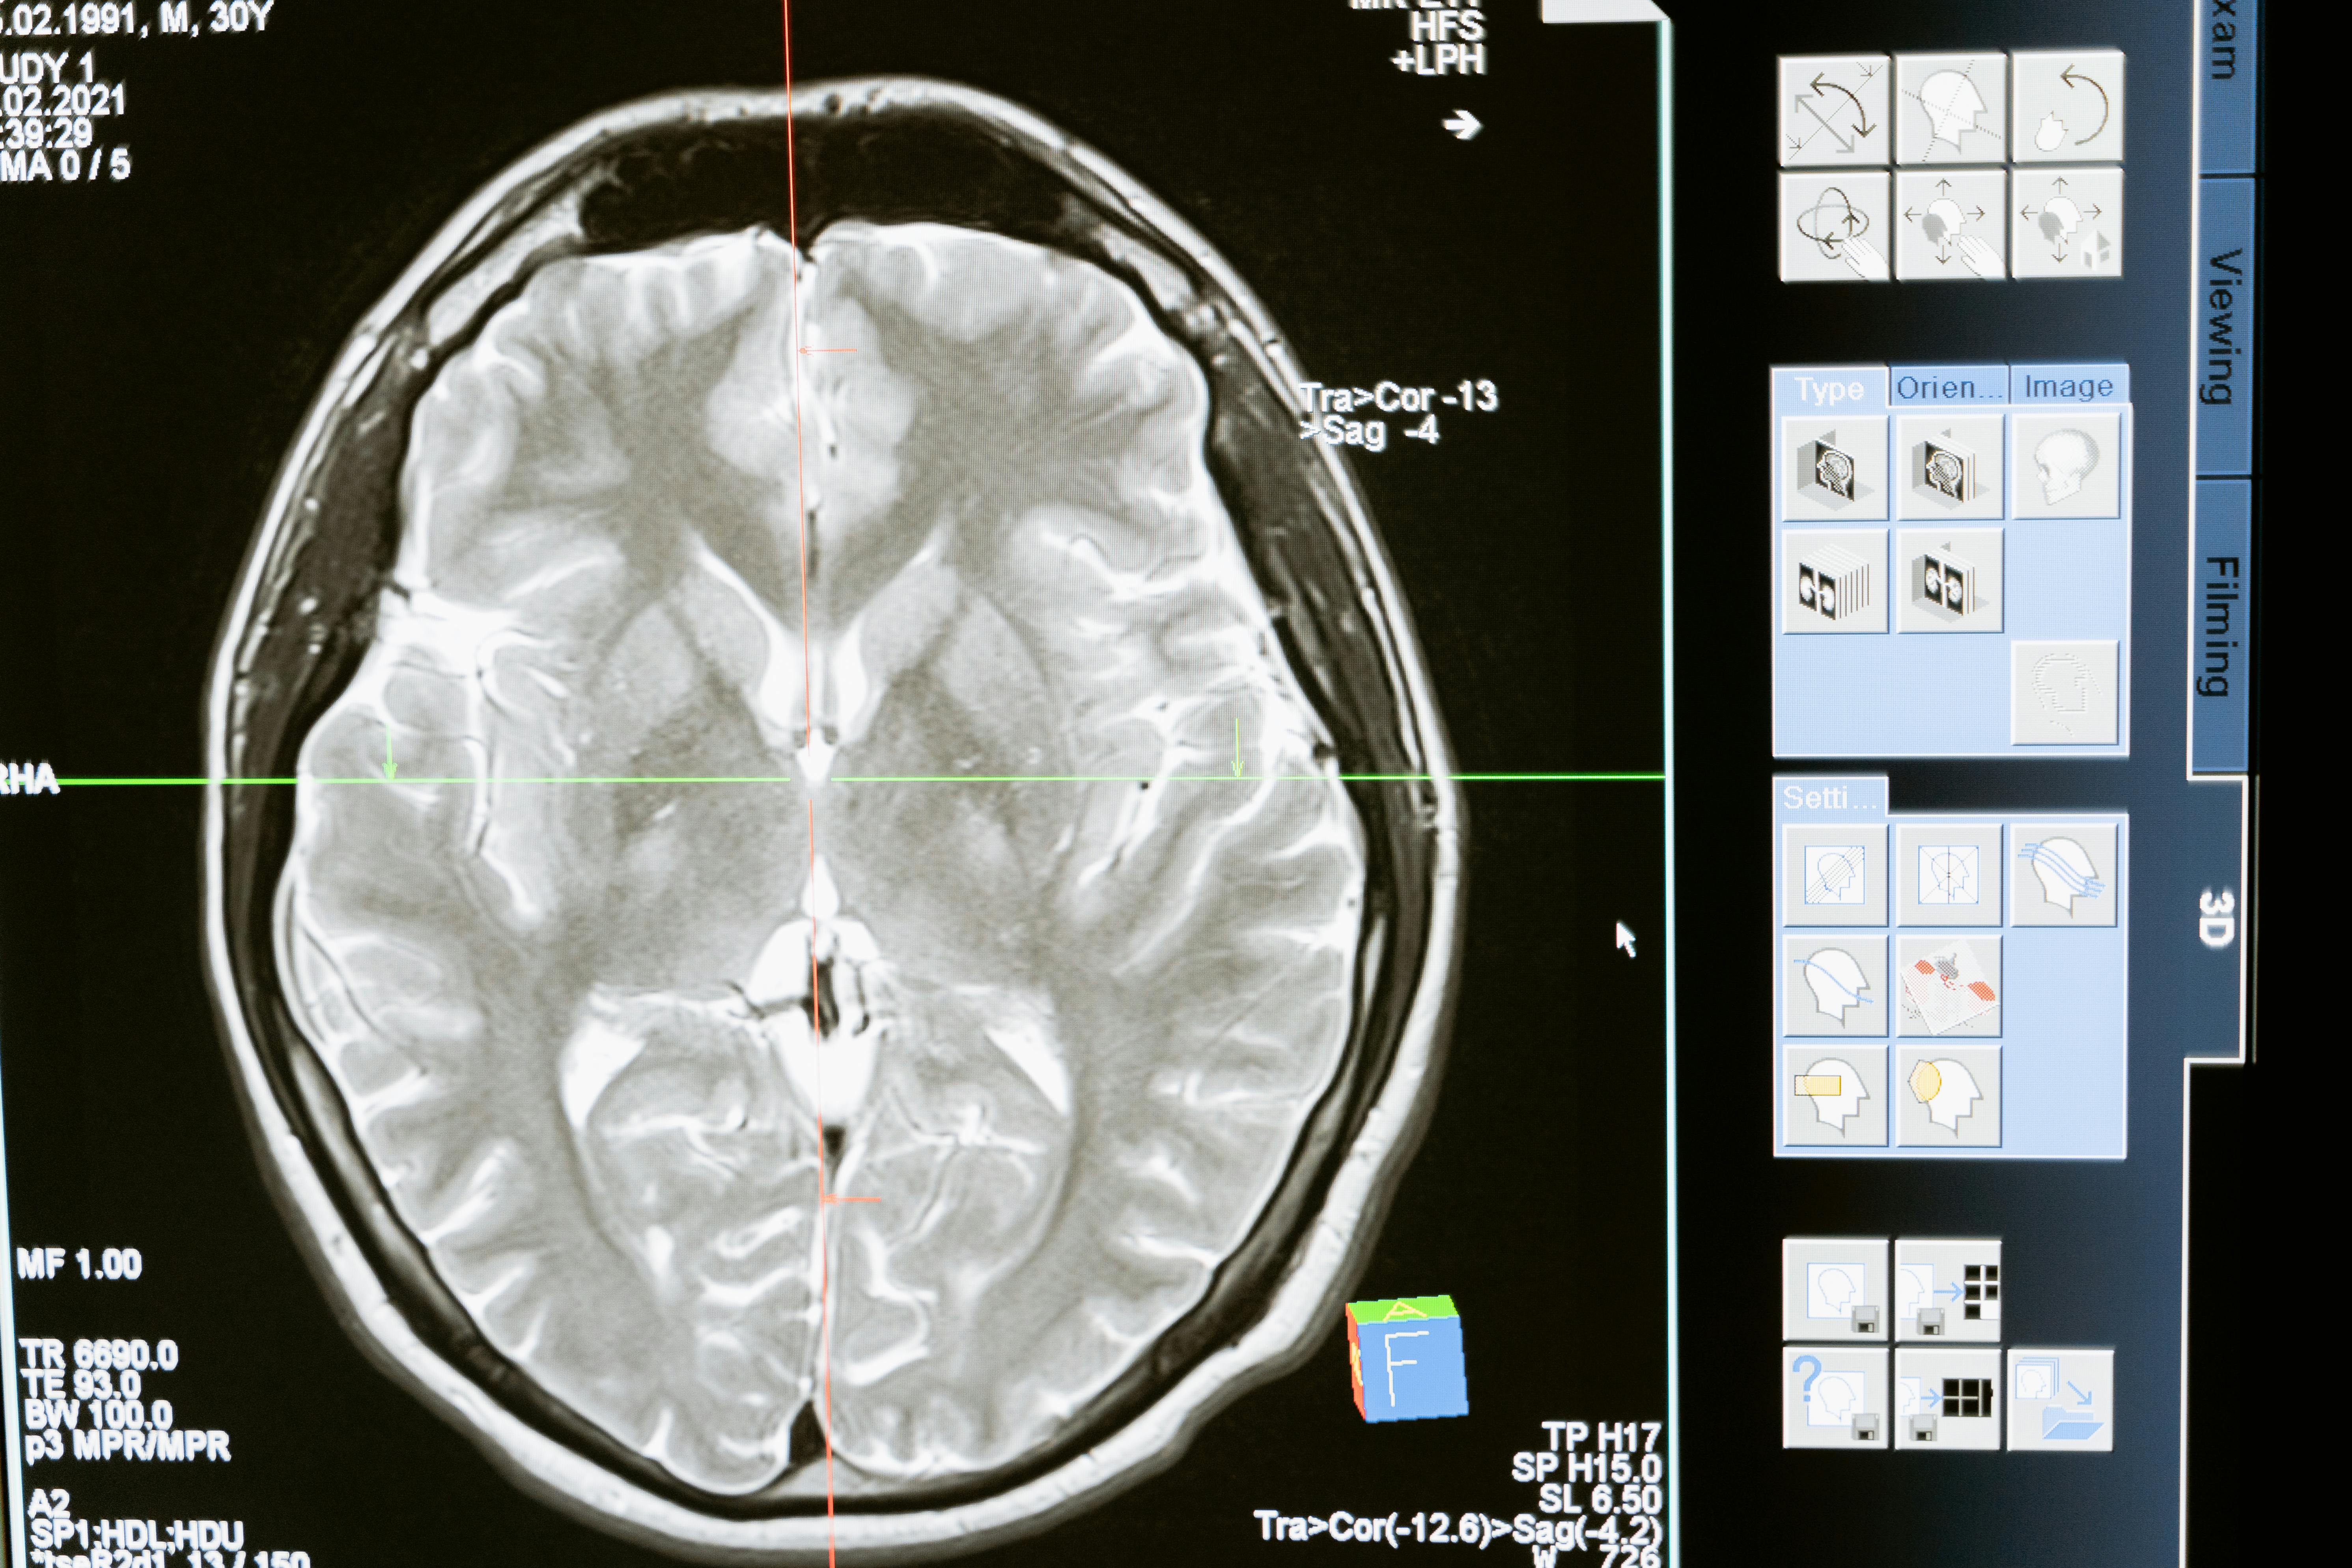

Een zwangere vrouw die alcohol drinkt tijdens haar zwangerschap loopt het risico om te bevallen van een kind met Foetaal Alcohol Spectrum Disorder (FASD). FASD is een overkoepelende term voor alle soorten aandoeningen die op deze manier bij ongeboren kinderen kunnen ontstaan. Foetaal-Alcoholsyndroom (FAS) is de meest voorkomende vorm, hierbij zijn de hersenen van het kind beschadigd door het alcoholgebruik van de moeder.

• Neurologische afwijkingen (kleinere hoofdomtrek)